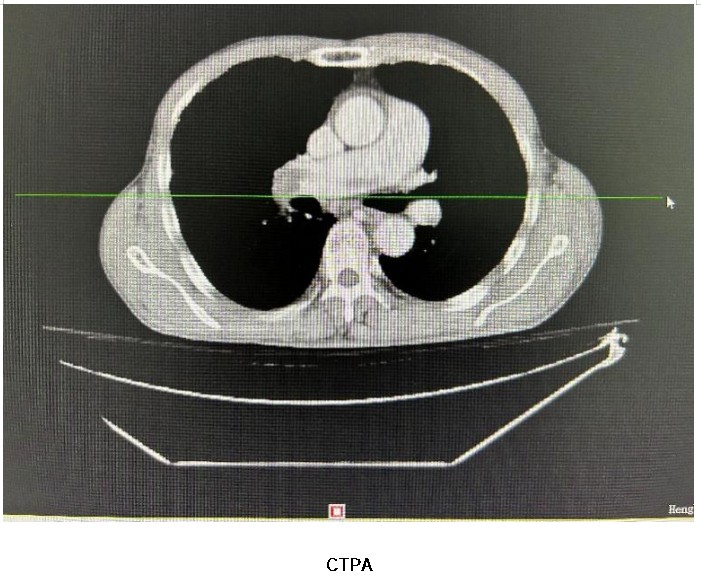

患者是68歲男性,胸悶、氣促4小時(shí),輕微活動(dòng)后加重,伴呼吸困難、輕度咳嗽,外院就診血氧飽和度60-70%(未吸氧狀態(tài))。為進(jìn)一步治療,至衡陽市中心醫(yī)院急診科就診。下肢深靜脈彩超提示雙下肢深靜脈血栓形成,主動(dòng)脈CTA提示肺動(dòng)脈栓塞(左右主干及分支)及雙側(cè)髂外、髂總、下腔靜脈栓塞,醫(yī)生診斷為“肺動(dòng)脈栓塞”后患者住院治療。

患者肺栓塞診斷明確,起病急驟,血栓負(fù)荷較大,為迅速清除血栓以降低其高危惡化風(fēng)險(xiǎn),涂宏主任團(tuán)隊(duì)與患者及家屬充分溝通病情后,決定實(shí)施肺動(dòng)脈機(jī)械取栓術(shù)。